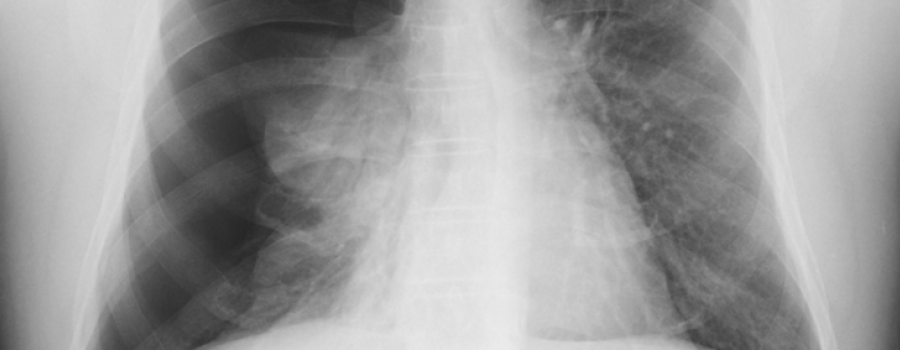

Was ist heute auf unserem ominösen Röntgenbild abgebildet?

Anamnese und Diagnose: - Der Patient hatte am Morgen einen Hustenanfall. Anschließend klagte er über rechtsthorakale Schmerzen und Luftnot. Am Nachmittag stellte er sich dann in der Notfallambulanz vor.